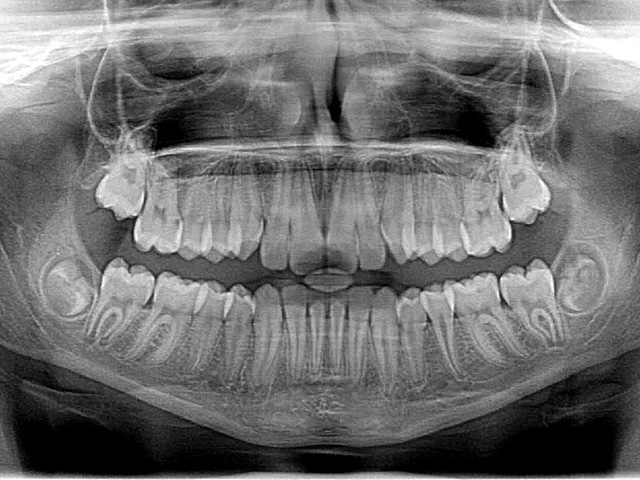

レントゲン、CT、口腔内写真、模型などを用いて、噛み合わせや顎骨の状態を詳しく確認します。